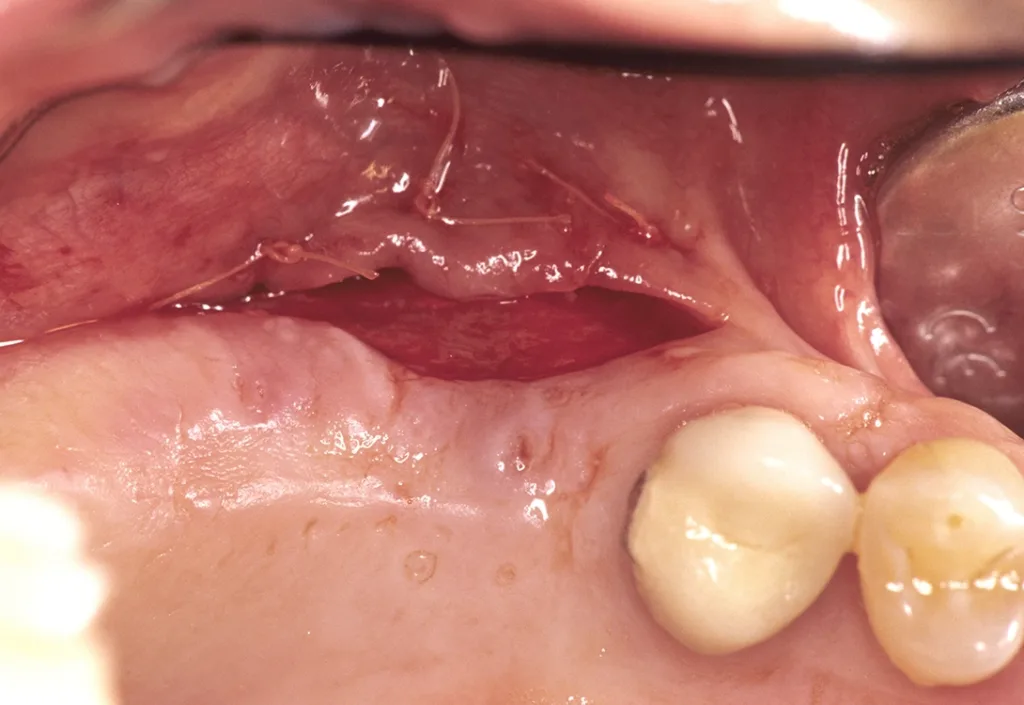

Zu den weit fortgeschrittenen Schäden mit zirkulärem trichterförmigem Implantatknochenabbau zählen Defekttiefen ≥ 8 mm: Explantation, ggfs. chirurgische Revision. Bei dieser Befundklasse umfassen die Empfehlungen zunehmend die Implantatentfernung mit Neuinsertion, ggfs. unter Augmentation und prothetischer Versorgung nach Ausheilung (bei Patientenwunsch). Der Vorteil einer rascheren Defektheilung bei Implantatknochenschäden nach Insertion dimensionsreduzierter Implantate liegt auf der Hand. Erfolgt im Einzelfall bei strategisch wichtigen Implantaten (Eckzahnbereich bei Zahnlosigkeit) die Entscheidung zur chirurgischen Revision, gilt folgender Behandlungsablauf [21]:

- Abnahme der Suprakonstruktion, wenn verschraubt

- horizontaler Kieferkammschnitt mit vertikaler Entlastung, Bildung eines Mukoperiostlappens

- Knochentaschenkürettage

- Spülung mit 0,2% CHX, ergänzend Er.YRG-Dekontamination

- Blutungsstimulation plus autogene Knochentransplantate zur Defektauffüllung und Rekonstruktion, ggfs. Abdeckung mit gestieltem und rotiertem Bindegewebslappen

- dichter, spannungsfreier Wundverschluss, keine funktionelle Belastung

- systemische Antibiose

Die chirurgische Revision trichterfömiger Implantatknochendefekte ist aufgrund ihres Zeitaufwands, Umfang und Kosten und begrenzter Indikationsstellung auf einzelne klinische Situationen begrenzt (Khoury und Buchmann 2001)